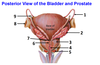

Where are the 3 potential sites of obstruction of the ureters in case of kidney stones?

- at the junction of the ureters and the renal pelvis

- where the ureters cross the brim of the pelvic inlet

- during their passage through the wall of the bladder